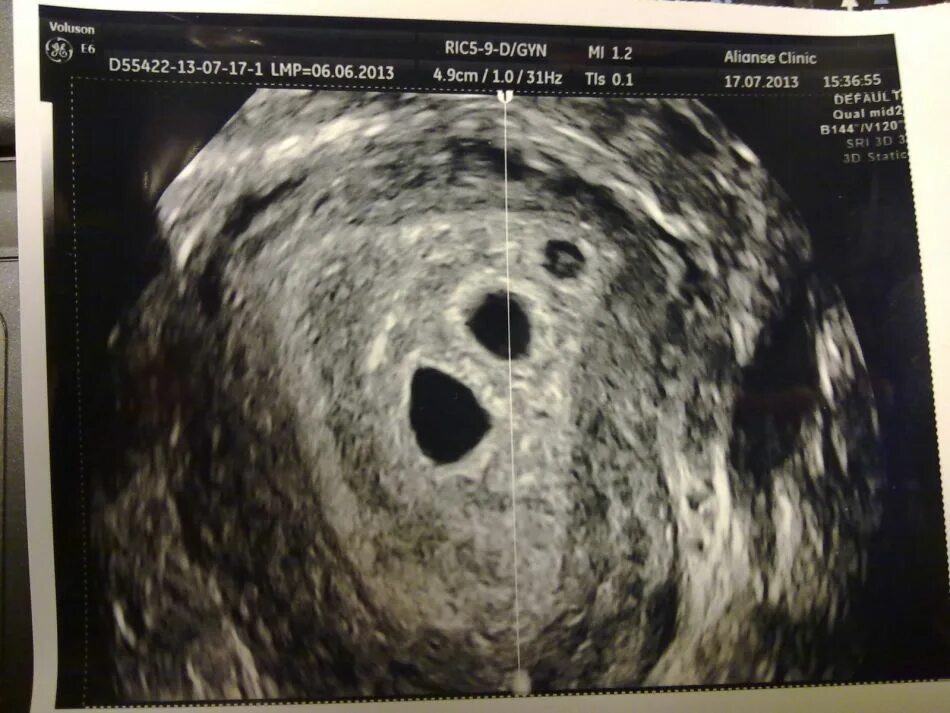

Увидят ли на 4 неделе беременность